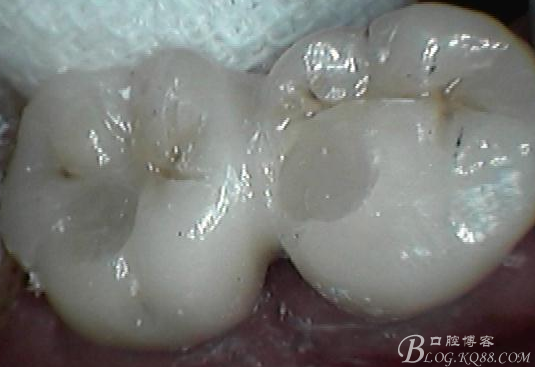

一月復查,上皮袖口封閉良好,牙齦恢復正常外形凸度,但近中齦乳頭仍不理想

試戴個性化基臺,牙齦外形穩(wěn)定

口外粘接后,口內螺絲固位

檢查邊緣封閉及靜態(tài)密合

牙齦封閉良好,咬合,近中觸點穩(wěn)定

樹脂封閉螺絲孔